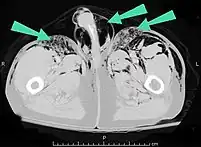

Infection

Air can be trapped under the skin in necrotizing infections such as gangrene, occurring as a late sign in gas gangrene,[2] of which it is the hallmark sign. Subcutaneous emphysema is also considered a hallmark of Fournier gangrene.[26] Symptoms of subcutaneous emphysema can result when infectious organisms produce gas by fermentation. When emphysema occurs due to infection, signs that the infection is systemic (i.e. that it has spread beyond the initial location) are also present.[9][21]

Significant cases of subcutaneous emphysema are easy to diagnose because of the characteristic signs of the condition.[1] In some cases, the signs are subtle, making diagnosis more difficult.[13] Medical imaging is used to diagnose the condition or confirm a diagnosis made using clinical signs. On a chest radiograph, subcutaneous emphysema may be seen as radiolucent striations in the pattern expected from the pectoralis major muscle group. Air in the subcutaneous tissues may interfere with radiography of the chest, potentially obscuring serious conditions such as pneumothorax.[18] It can also reduce the effectiveness of chest ultrasound.[27] On the other hand, since subcutaneous emphysema may become apparent in chest X-rays before a pneumothorax does, its presence may be used to infer that of the latter injury.[13] Subcutaneous emphysema can also be seen in CT scans, with the air pockets appearing as dark areas. CT scanning is so sensitive that it commonly makes it possible to find the exact spot from which air is entering the soft tissues.[13] In 1944, M.T. Macklin and C.C. Macklin published further insights into the pathophysiology of spontaneous Macklin's Syndrome occurring as a result of a severe asthmatic attack.